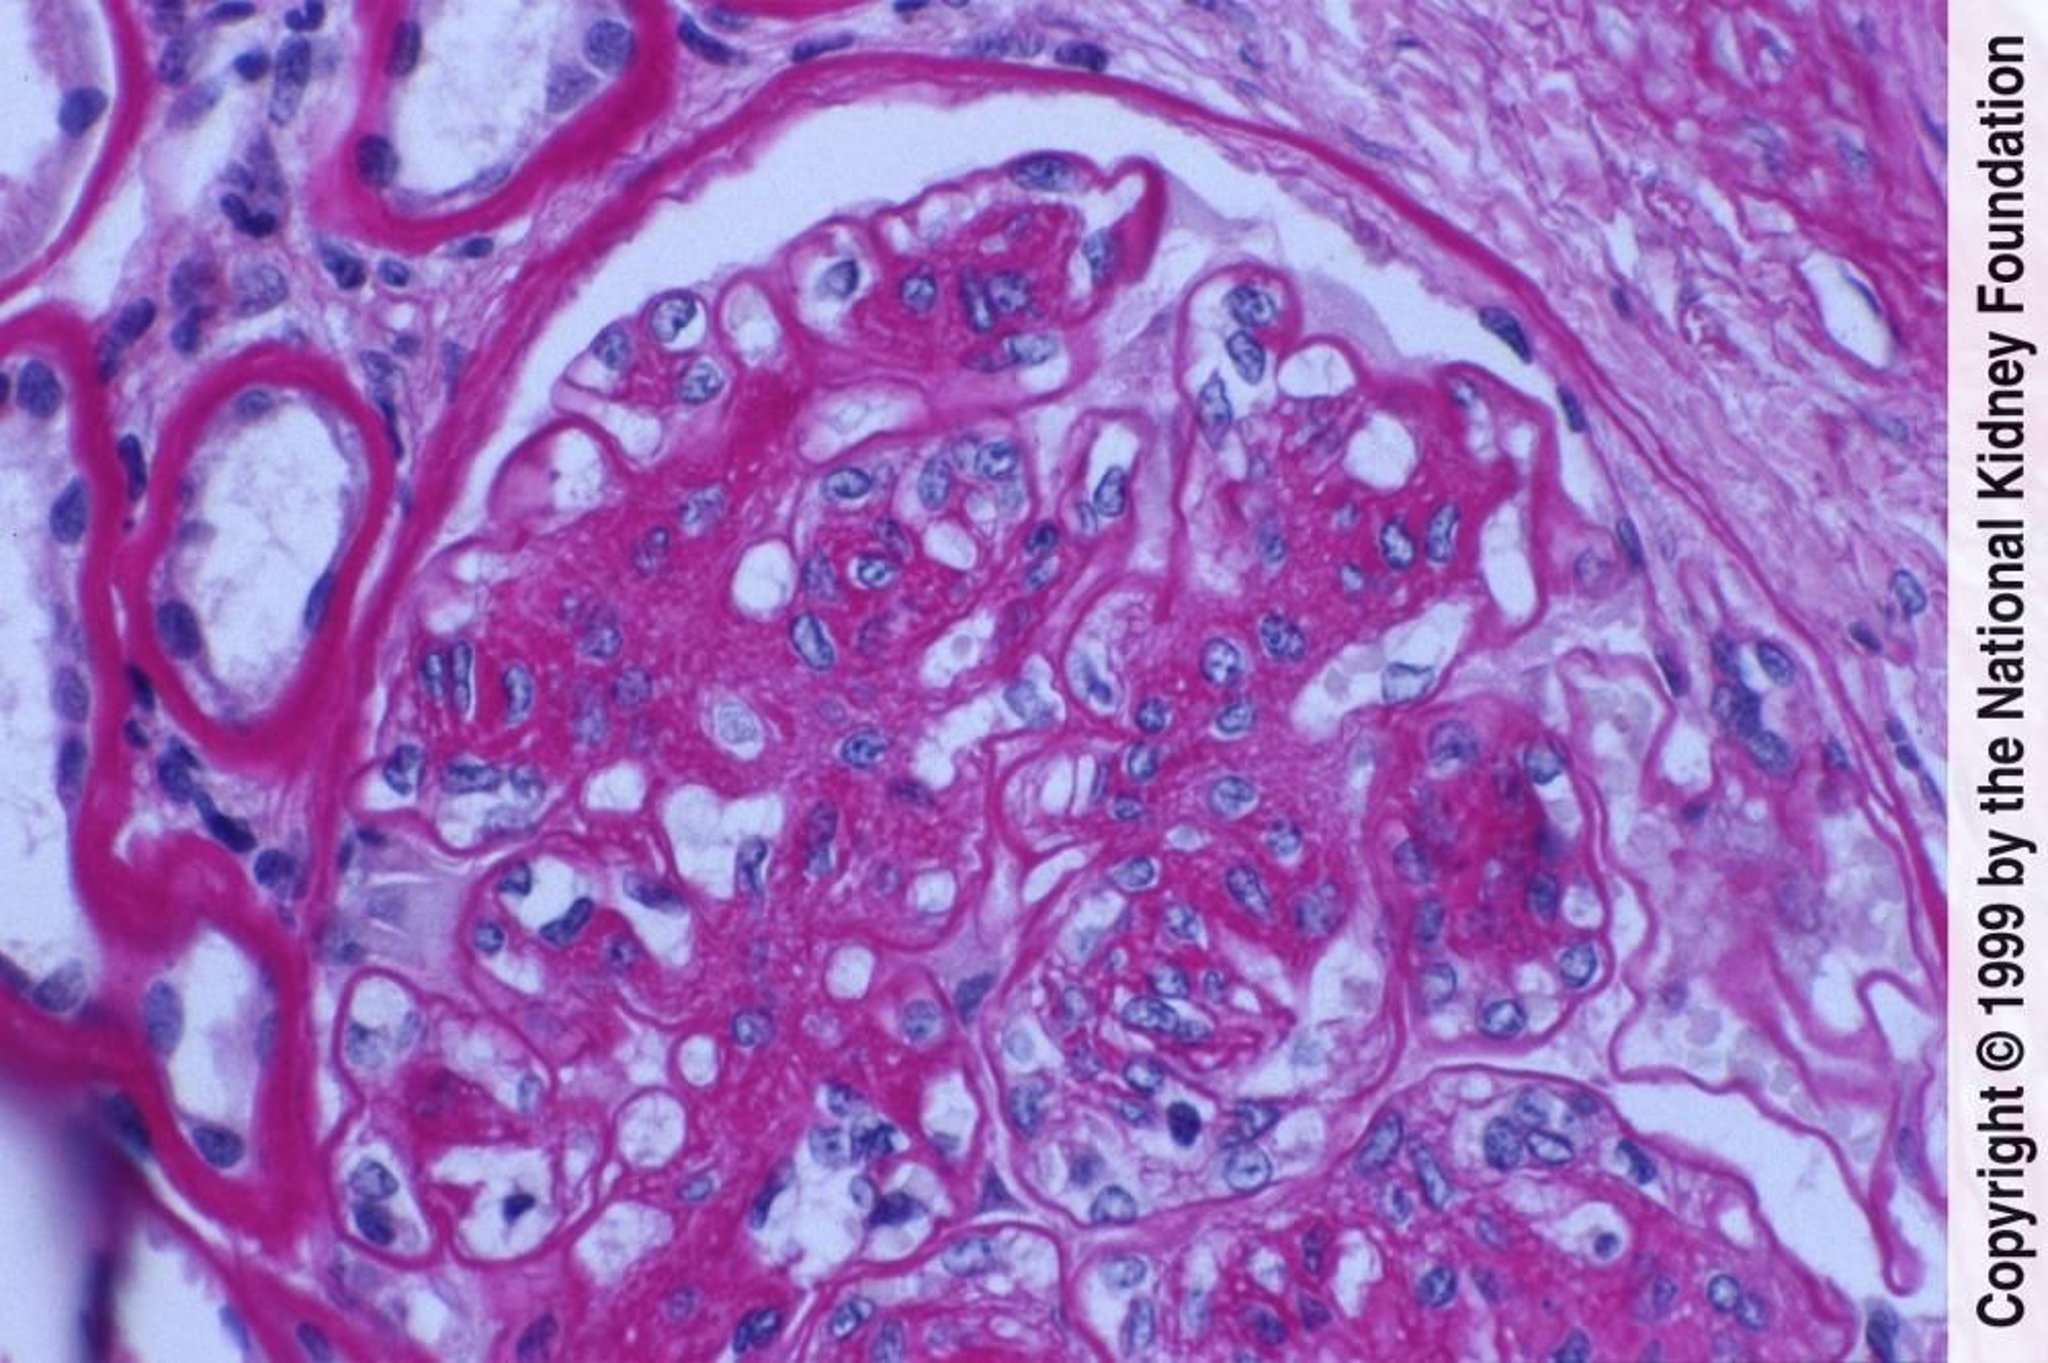

Nefropatia diabética (proliferação de células mesangiais e expansão da matriz)

A proliferação de células mesangiais e a expansão da matriz com lesão endotelial se manifestam aqui como espessamento das membranas basais glomerulares sem depósitos evidentes de imunocomplexos (coloração com ácido periódico de Schiff, × 400).

Image provided by Agnes Fogo, MD, and the American Journal of Kidney Diseases' Atlas of Renal Pathology (see www.ajkd.org).